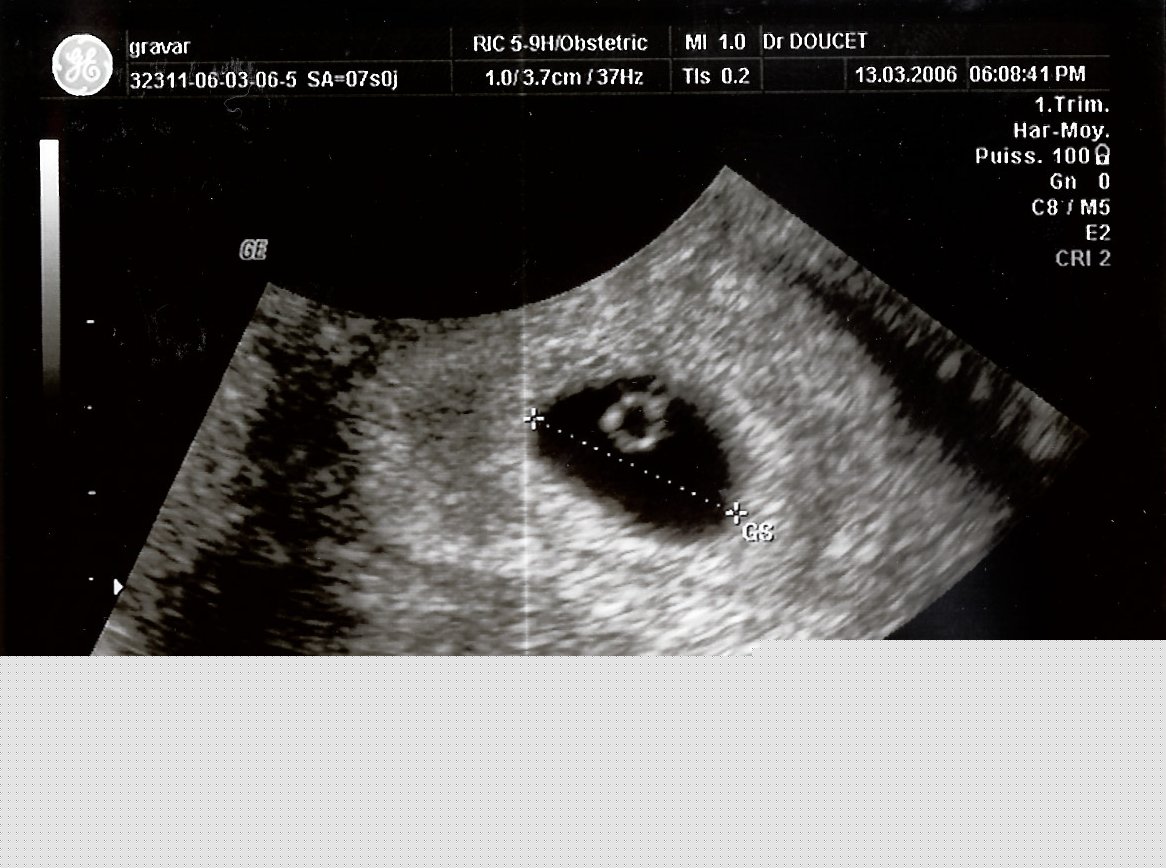

13 mars 2006 - Echographie

Le 13 mars 2006, on me prend en photo pour la première fois. Je ne ressemble pas encore à grand chose, il faut bien le reconnaître.

Mais bon, ce docteur avait raison, Maman a bien un sac dans le ventre.

Maman et Papa découvrent mon existence. Monsieur Doucet nous annonce que Maman a un petit sac dans le ventre.